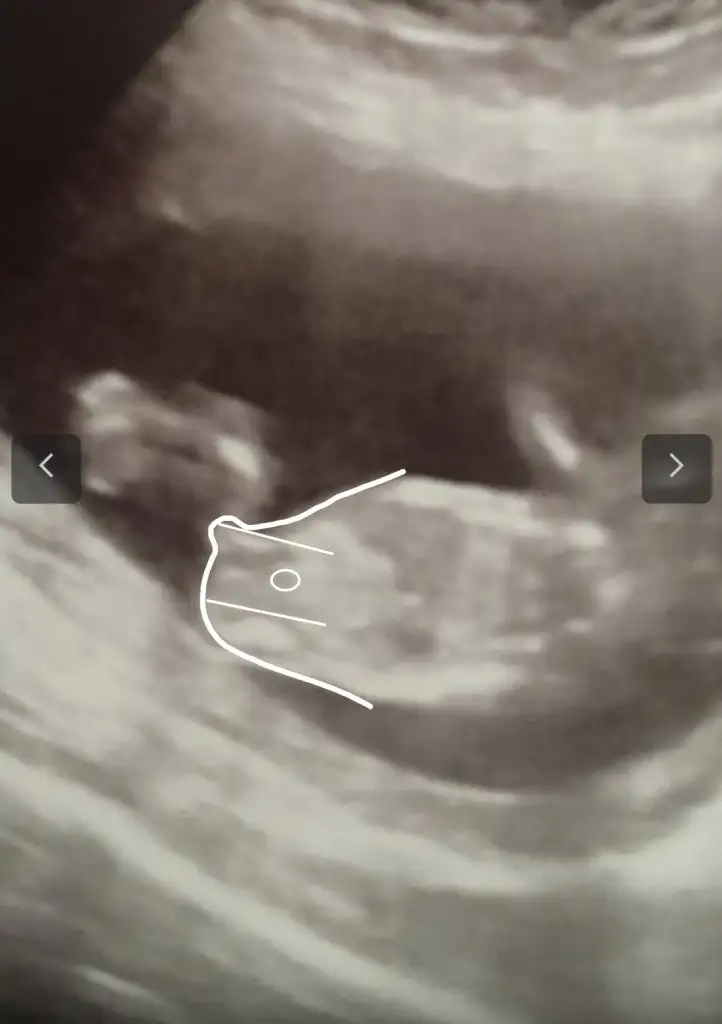

USG göre kız gibiydi sağlıkla gelsin oğlusun bakın benim suçum yok çizdim Eki Görüntüle 2819617

Çok teşekkürler. Ramiz teorisine göre de kız demişti arkadaş vlla ne yalan söyleyeyim bende kız istiyordum bi oğlum vardı. Nasip gördük bugün pipiyi 16. Haftadayız değişmez herhalde